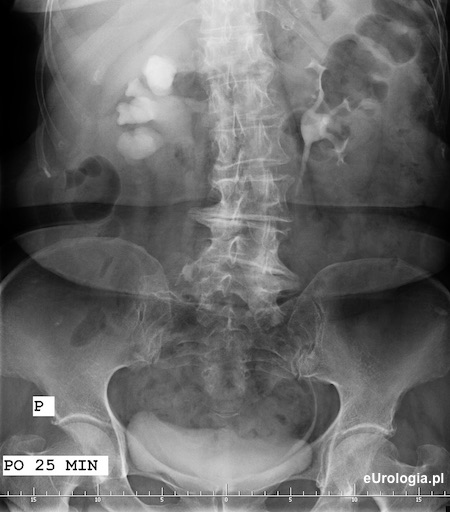

Zdjęcie po 15 minutach po podaniu kontrastu - wodonerczowato poszerzony UKM prawej nerki. Układ kielichowo-miedniczkowy nerk lewej i moczowód lewy na całej długości wypełnione zakontrastowanym moczem

Wodonerczowo poszerzony UKM prawej nerki i poszerzony górny odcinek moczowodu aż do opisywanego na zdjęciu przeglądowym cienia - złóg w moczowodzie.

Zółtą strzałką oznaczono cień wapienny o wymiarach 11x8 mm będący złogiem w górnym odcinku prawego moczowodu.